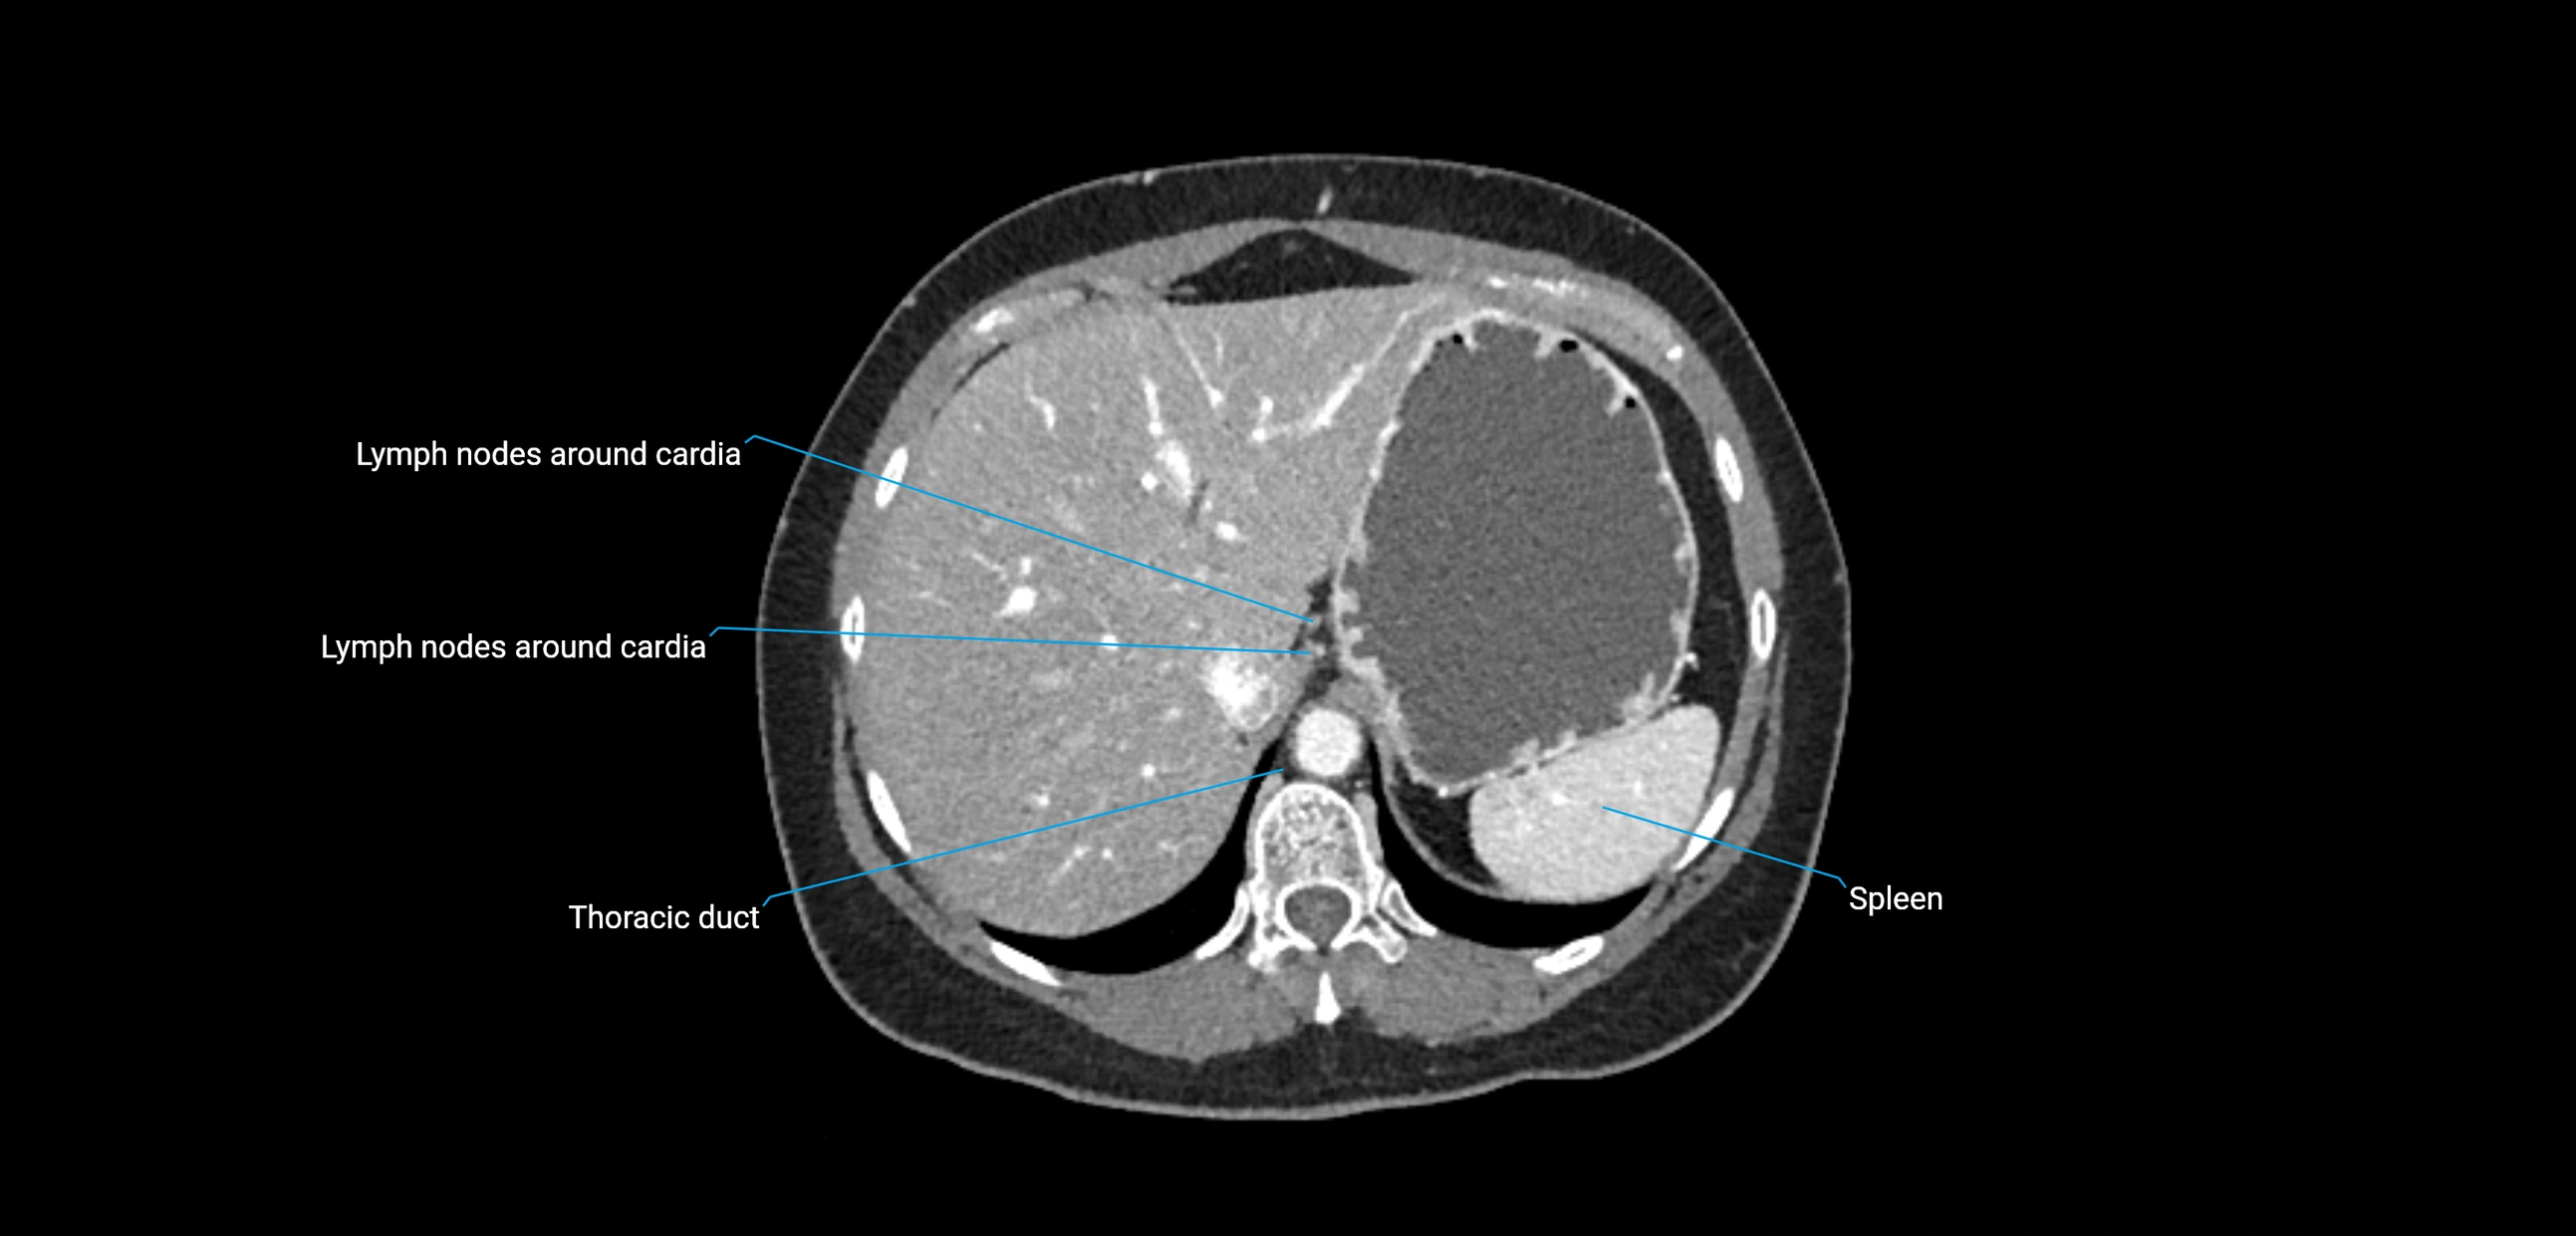

CT Appearance

CT Pre-Contrast:

• Nodes appear as soft-tissue density nodules adjacent to the aorta and IVC

• Calcification may be seen in chronic infections (e.g., tuberculosis)

CT Post-Contrast:

• Normal nodes enhance homogeneously

• Malignant nodes may show heterogeneous enhancement, central necrosis, or conglomerate formation

• Size >1 cm short axis is suspicious, though morphology and distribution are equally important